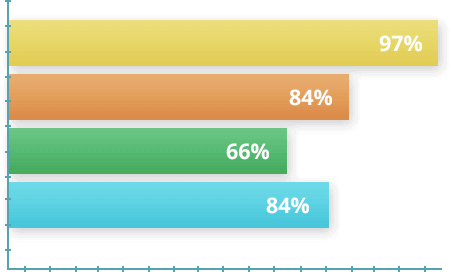

FÜGGETLEN TANULMÁNYOK BIZONYÍTOTTÁK A Remofix GÉL HATÉKONYSÁGÁT.

Egy 2017-es vizsgálatban 1700 önkéntes vett részt, akik különböző mértékű ízületi károsodásban szenvedtek. A feltételek szerint az alanyok 30 napig használták a Remofix gélt. A kísérlet végén a kapott adatok alapján statisztikákat készítettek.

- A résztvevők 97%-a érezte a fájdalom gyors enyhülését

- A résztvevők 84%-a 1 kúra alatt megszabadult az ízületi problémáktól.

- A résztvevők 66%-a visszatért a sporthoz a kúra elvégzése után.

- A résztvevők 84%-a számolt be arról, hogy javult az ízületek mozgékonysága a korábbi állapotukhoz képest.